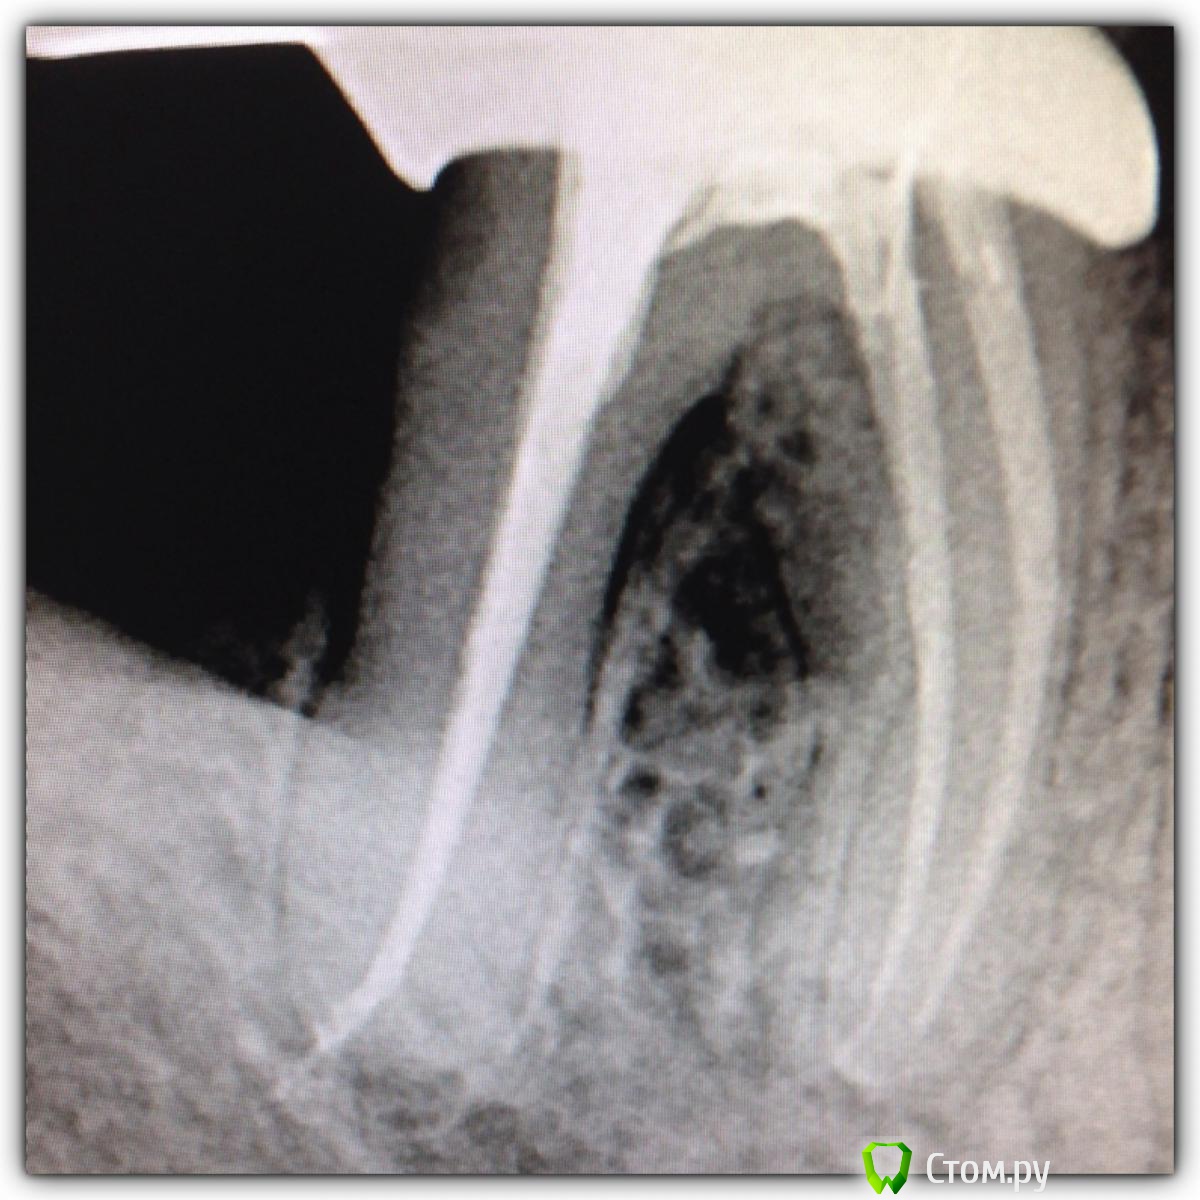

SSTi Опубликовано 9 октября, 2014 Автор Поделиться Опубликовано 9 октября, 2014 Двойка того же пациента. Тоже пошла по наклонной. Пульпит. Мш 80. Но. Апекс цел и невридим. 20ка упиралась спокойно. А мм до апекса - 80 Жаль дельта не пропаковалась. Мыл усердно 2 Ссылка на комментарий

SSTi Опубликовано 9 октября, 2014 Автор Поделиться Опубликовано 9 октября, 2014 Это канал с обратной конусностью)))) 1 Ссылка на комментарий

SSTi Опубликовано 15 октября, 2014 Автор Поделиться Опубликовано 15 октября, 2014 Продолжение истории сообщения 107. Прошло 5 месяцев. Пациент забежал сегодня записаться. Заодно сфоткались. Углы разные. И верхняя единица. Что думаете? 7 Ссылка на комментарий